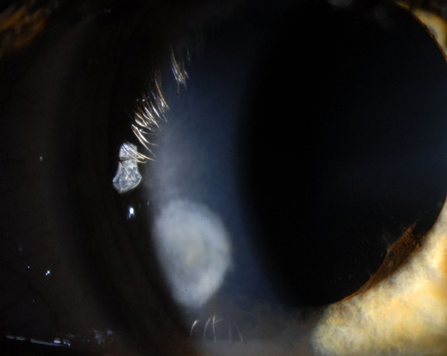

A 28-year-old female patient presented with a medical history significant for contact lens associated keratitis. She had been treated with several different topical antibiotics for almost three months due to contact lens associated corneal infiltration. Due to increasing anterior chamber involvement, local and systemic steroids had been added after one month. Since the patient’s symptoms failed to improve, she was referred to our clinic. Best corrected visual acuity was 8/20 on her right eye and 20/20 on her left. Intraocular pressure was normal. Slit lamp examination revealed on the right eye a peripheral corneal infiltration with a central ulcer, a deep anterior chamber with a mass on the iris and a hypopyon (Figure 1 [Fig. 1]). These features evoked suspicion of a fungal intraocular infection. Steroids were stopped and a biopsy of the mass was performed with bimanual irrigation and aspiration handpiece use (Figure 2 [Fig. 2]). Topical treatment with Natamycin 5% and Voriconazole 1.9% eye drops was started hourly, and initially Voriconazole 400 mg intravenously was also given twice a day. First specimen taken showed Fusarium spp. without further subdifferentiation. Intracameral lavage with Amphotericin B (7.4 µg) was performed by tap and inject in the operating room. A second specimen was taken with bimanual irrigation and aspiration handpiece use for further subdifferentiation and antifungal drug susceptibility testing after 3 injections of Amphotericin B.

Figure 1: Slit-lamp photo of the right eye showing hypopyon and fungal mass in the anterior chamber (day 1)